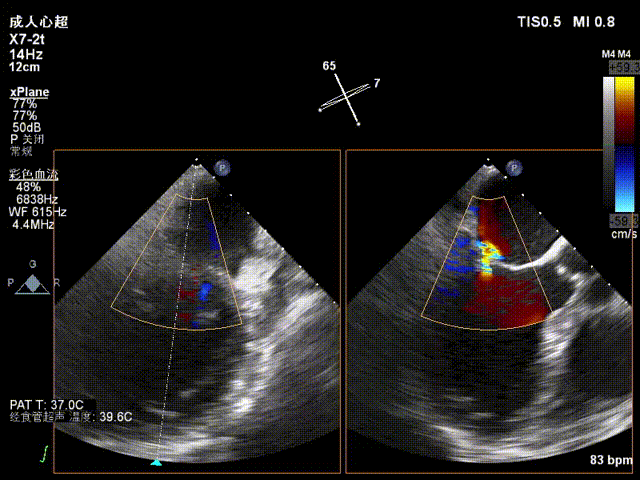

术后超声评估

术后TEE显示二尖瓣双孔化形成,反流明显减少,瓣膜夹位置稳定,二尖瓣跨瓣平均压力阶差为4mmHg,植入后反流下降至1+